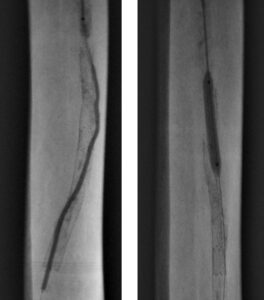

Figure 2. Gradual balloon dilation upsizing from 4-6 mm diameter outside the stent

Access was gained in the left common femoral artery. We advanced a 7-frech Pinnacle 65cm sheath up and over to the right CFA. We were able to probe the vessel outside the previously occluded stent and gain access to the true lumen of the vessel beyond the occluded stent in the distal right SFA. A number of wires were used, including stiff Glidewire and an Amplatz wire. The stiff straight guidewire was used, along with a vertebral catheter, QuickCross catheter, and Trailblazer 0.035 catheter. We dilated the vessels with a 3.5mm Nanocross balloon. We then dilated the right superficial femoral artery with a 6mm balloon, followed by a 7mm balloon. After dilation, right SFA occlusion went from 100% to 60% severe recoil. We deployed 6×120 and 6×80 Supera stents, overlapping them with care to improve stacking of the stents to optimize radial strength. This was in the mid to distal SFA. The completion angiogram revealed a good result, with less than 20% residual stenosis at the SFA post double-barrel stenting. Patient tolerated the procedure well and was kept on DAPT.